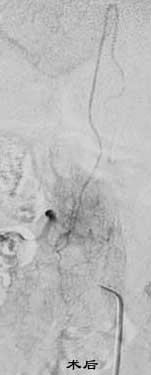

二、脑动静脉畸形(AVM)

---- Spetzler对AVM的分级方法已越来越多地被人们接纳和采用。脑AVM最危险的症状之一是出血。AVM每年的出血率为 3%~4%,第一年内再出血约6%。每次出血的致残率为30%,病死率为12.5%,而积极治疗的总残废率加病死率在10%以下。

---- 血管内栓塞对于单支或少数供血动脉的AVM,特别是新近出血的病例,可以达到微侵袭、痛苦小、疗效迅速的目的。 近来改变栓塞方式,将导管直接放置 畸形血管团内,注射NBCA胶,可使畸形团的解剖 治愈率提高至27%。再加上更细、超 滑的微导管问世,栓塞的并发症更为降低。针对大型、功能区 的AVM栓 塞可缩小其体积,改善血液动力学分布,以利于显 微外科技术切除或放射外科治疗,是后二者的重要辅助手段。